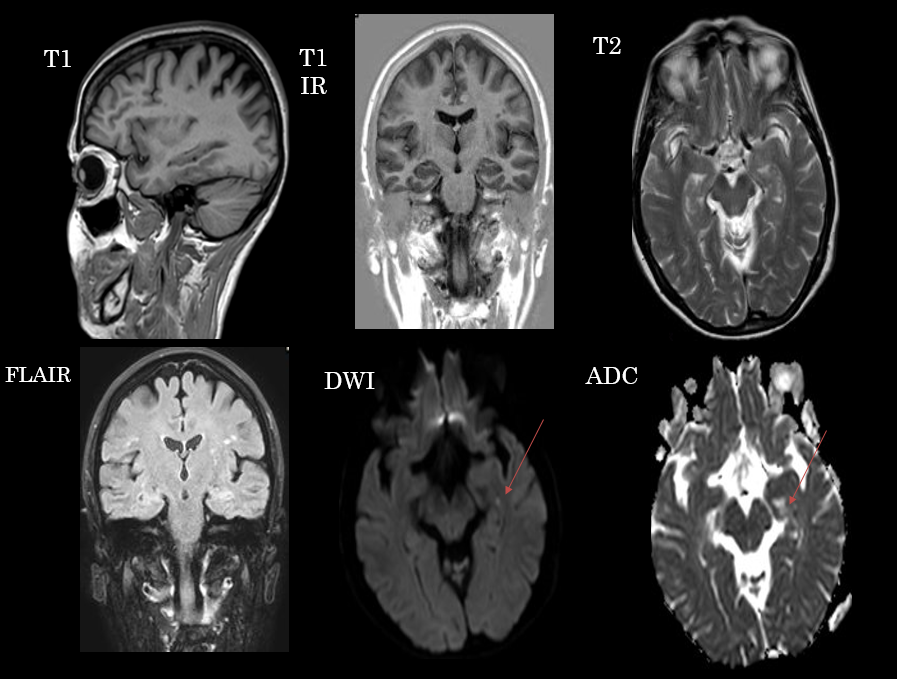

Secuencias de RM sin contraste intravenoso. En difusión se aprecia un foco de restricción puntiforme en hipocampo, que no se manifiesta en otras secuencias.

Lesiones puntiformes en secuencia de difusión en el contexto de amnesia global transitoria.

- Típicamente focos puntiformes que restringen en difusión localizados en hipocampo que suelen ser unilaterales y de predominio en lóbulo temporal izquierdo, aunque pueden ser bilaterales. En ocasiones pueden observarse como lesiones hiperintensas en las secuencias potenciadas en T2. Típicamente suelen desaparecer en control posteriores (>2 semanas).

- La fisiopatología no está clara, habiéndose relacionado con fenómenos isquémicos (tales como AIT), migraña, epilepsia y recientemente con fenómenos de congestión venosa poco estudiados. La restricción en difusión (en ocasiones reversible) podría sugerir edema citotóxico como parte de la fisiopatología del cuadro.